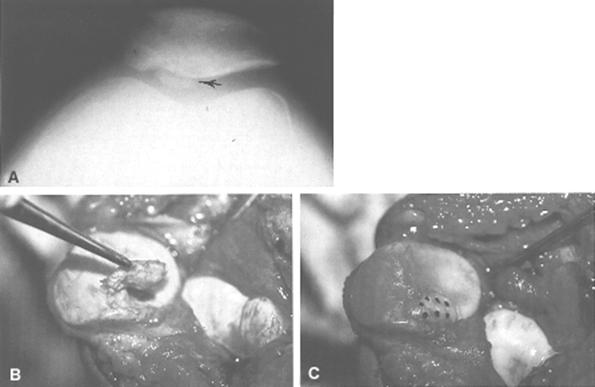

When the chondral injury is associated with subchondral bone involvement, the subsequent radiopaque injury, a loose body, will be readily apparent on standard roentgenograms. It is important, however, to get more than just anteroposterior and lateral views (Fig. 29-61). In patients in the second to fourth decades of life, who are most susceptible to these types of injuries, tangential patella (Fig. 29-62A) and tunnel views should be obtained. Tunnel views are particularly important in patients susceptible to osteochondritis dissecans (Fig. 29-63). This lesion, most often seen on the lateral aspect of the medial femoral condyle, is usually unilateral (74%) and is twice as common in males.187,188 The age of affected persons ranges from 6 to 53, but the classical presentation occurs in those under age 18. Proposed etiologies are diffuse, and radiographically one must be careful not to confuse this with a normal growth plate.212 Similarly, osteochondritis dissecans of the patella is less common and might be mistaken for an osteochondral fracture of the patella (see Fig. 29-37).200,205,216 Avulsion injuries at the inferior pole of the patella216,223,231 also must not be confused with osteochondral fractures of the patella.

Fig.28-62 A) Fractura osteocondrala

Open reduction and internal fixation of osteochondral fractures have been attempted with Kirschner wires and screws. Long-term results with these treatments do not favor either technique; in fact, several large series report good results after removal of the osteochondral fragment.186,189,215,228,235,237 In general, small fragments need not be replaced, but when there are large fragments composing at least 25% of the joint surface area, consideration must be given to replacing the fracture fragment. In these cases, care should be taken that any internal fixation device does not interfere with the tibial and femoral articulation. In addition to the Herbert screw biodegradable pins (Orthosorb) and fibrin adhesive material have recently been introduced to promote fixation and healing of these fragments (see Fig. 29-62B and C). Experience to date is insufficient to formulate any definitive opinions.242

We do not replace pieces of articular cartilage unless they are acute, large osteochondral fractures that are amenable to fixation. There is no rule as to what size fragment should be removed, but with a fragment in excess of 25% of the joint surface, we often attempt to reposition it (see Fig. 29-62).